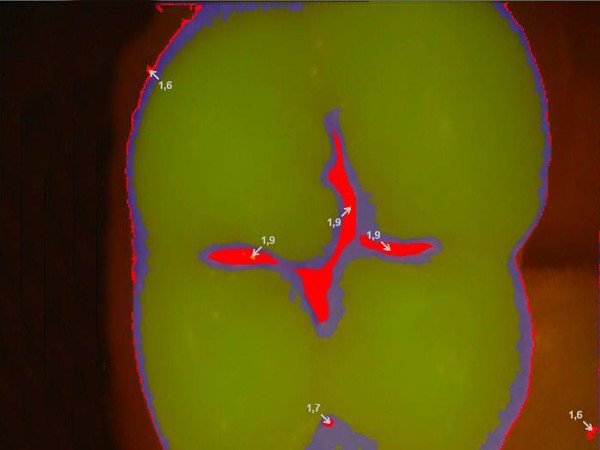

VistaCam iX dựa trên hiện tượng các tổn thương trên răng (như sâu răng) sẽ phát huỳnh quang khác với các mô lành khi bị kích thích bởi ánh sáng ở các bước sóng cụ thể. VistaCam iX [Durr Dental, Đức] sử dụng gallium nitride điốt phát ra ánh sáng màu xanh trên bề mặt răng. Ánh sáng phát ra từ bước sóng này kích thích porphyrin có trong vi khuẩn gây bệnh phát ra ánh sáng đỏ, chứa ít năng lượng hơn, ngược lại với men âm phát ra ánh sáng xanh lục. Những khác biệt này được camera ghi lại, chuyển sang máy tính và xử lý bằng phần mềm DBSWIN [Dürr Dental, Đức]. Sau đó, hình ảnh kỹ thuật số được tạo ra, hiển thị các tổn thương với các màu sắc khác nhau và thông tin số về độ sâu của sâu răng cũng được cung cấp.

Theo đó, giá trị ≥1,0 được coi là bằng chứng về sự bắt đầu của sâu răng men, trong khi sâu răng có trị số ≥2,0. Các nghiên cứu trước đây về đặc hiệu tối ưu đã chỉ ra rằng điểm này nên được đặt ở 1,4/1,5 để phát hiện các tổn thương ở đường gân một cách thích hợp, có nghĩa là các tổn thương > 1,5 có thể được coi là dấu hiệu tổn thương răng.